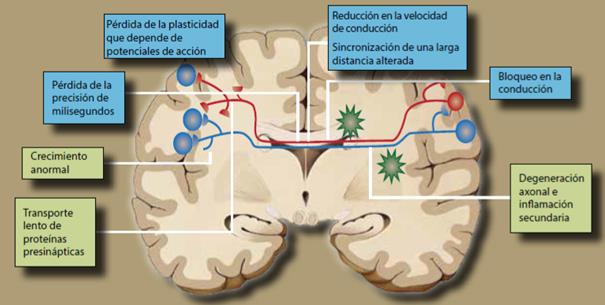

Debido a las limitaciones impuestas al nacimiento por las características que dan origen al dilema obstétrico, el neonato tiene que continuar su maduración cuando ya se encuentra fuera de la madre. Estos pasos implican una gran cantidad de ajustes en todo el cuerpo, pero aquí sólo mostramos unos cuantos que están relacionados con las funciones superiores del sistema nervioso y que pueden ser producidos por deficiencias en el proceso de la mielinización. Éstos se muestran en la figura 13, donde puede verse que al perderse la sincronía en la señalización entre las diferentes regiones del cerebro, se pierde también la capacidad para la comunicación apropiada del cerebro, lo que resulta en alteraciones en funciones nerviosas críticas.

La mielinización de los axones neuronales por las células gliales (oligodendrocitos y células de Schwann) es esencial para la conducción rápida de los impulsos nerviosos. Esta mielinización es un proceso complicado que in vivo es estrictamente regulado por una serie de factores, entre los cuales el más crítico parece ser la enzima nardilysin (N-arginina dibásico convertasa [NRDc]), que regula la maduración axonal porque la mielinización es proporcional al diámetro axonal28.

La maduración y mielinización son esenciales para la conducción nerviosa y en varias patologías son aberrantes. Por ejemplo, el evento patológico primario en la esclerosis múltiple es la desmielinización, mientras que la remielinización se correlaciona con la recuperación de los síntomas clínicos. En la misma forma, una perturbación durante el proceso de la mielinización en cualquiera de sus etapas, pero más aún cuando se empiezan a mielinizar las fibras que llevan las señales entre el tálamo y la corteza cerebral, podría llevar a alteraciones cuyas consecuencias no serían vistas sino de forma tardía.

Entre las enfermedades que podrían ser explicadas como consecuencia de problemas durante el nacimiento de fetos grandes que pasaron a través de anillos pélvicos estrechos se encuentra la esquizofrenia, una enfermedad que se inicia durante la época en que el niño está saliendo de esta etapa, pero que se manifiesta hasta muchos años después, durante la edad adulta temprana. La esquizofrenia es un síndrome, una colección de signos y síntomas de etiología desconocida, pero definida por signos de psicosis y, en su forma más común, por delusiones paranoides y alucinaciones auditivas en la adolescencia tardía e inicio de la madurez.

Son particularmente notables las numerosas etiologías que se han propuesto para explicar la esquizofrenia, desde alteraciones en la mayor parte de los neurotransmisores y receptores conocidos, hasta condiciones medioambientales e incluso astronómicas. Sin embargo, una de las condiciones más estudiadas actualmente es la conexión que parece existir entre la esquizofrenia y las alteraciones en la sustancia blanca del cerebro, que está formada principalmente por las vainas de mielina de los axones que conectan las diferentes regiones del cerebro29. Afortunadamente las grandes máquinas que están proporcionando ayuda al diagnóstico de las enfermedades mentales, como la resonancia magnética, el análisis de tensores y otras, ya están produciendo datos que ayudarán en las investigaciones sobre la etiología de esta enfermedad tan común en el mundo moderno 30.

Por ahora ya se sabe que la etapa en que se inicia la esquizofrenia es la misma durante la que ocurre la mielinización de los axones en el sistema nervioso central, por lo que una alteración en este proceso tendría consecuencias en la formación de los circuitos cerebrales. Si esta hipótesis se mantiene, entonces es posible que el problema se inicie debido a una lesión del cerebro durante la etapa del nacimiento, por ejemplo debido a que al pasar por un canal pélvico demasiado estrecho, la cabeza grande del feto a término podría sufrir una compresión que produzca daño en regiones cerebrales en formación. Por supuesto, hay otras posibilidades, como un exceso en la poda de neuronas durante el desarrollo, por lo que actualmente la alteración en la mielinización es todavía una hipótesis que debe ser confirmada.